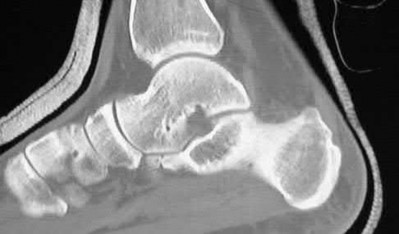

A 34-year-old male sustains the closed injury seen in Figure A as a result of a high-speed motor vehicle collision. What is the most appropriate next step in treatment?

The radiograph shows a comminuted pilon fracture, which is associated with high-energy trauma and significant soft tissue injury. The tested concept here is the importance of avoiding definitive reduction and fixation of this high-energy injury, which has been shown to be associated with an increased risk of wound complications and deep infections (as compared to staged treatment with usage of a spanning external fixator).

Patterson et al. reviewed 23 consecutive patients with comminuted distal tibia fractures. They showed 0% infections or wound-healing problems in their patient population treated with a two-staged protocol. Their protocol involved fibula fixation with an intramedullary implant and application of a medial external fixator to to regain length and restore anatomic alignment. Reevaluation of the limb occurred ten to fourteen days later for definitive fixation.

Sirkin et al. retrospectively reviewed 40 closed and 17 open pilon fractures (AO types 43A-C) that were treated with staged surgical management (avg. time from ext. fix. to formal reconstruction was 14 days (range 4 to 31) They reported 17% post-operative wound complication in the closed group and 11% post-operative wound complication in the open group (Gustilo Type I-III). They suggest the technique was successful in both closed and open pilon fractures.